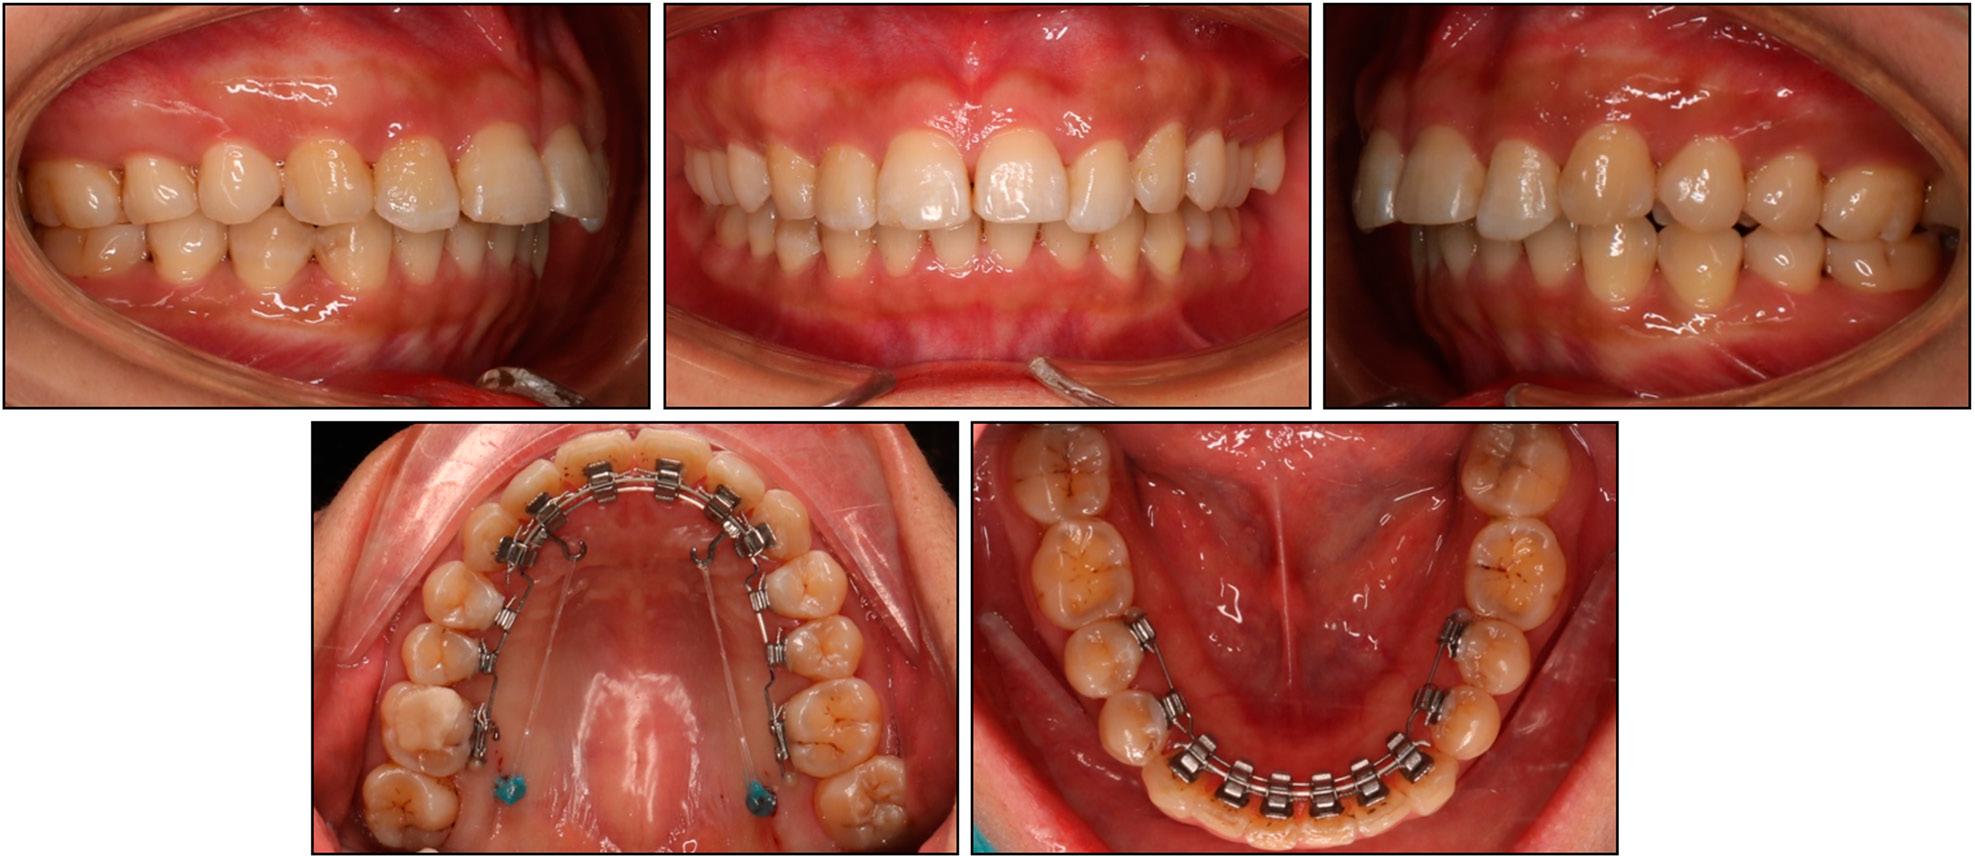

A 30-year-old female patient presented with a request to have her palatally inclined upper incisors, deep bite, and gummy smile corrected using an aesthetic appliance. Her medical and dental histories were non-contributory.

From the frontal view, the patient exhibited a short lower facial third with a slight chin deviation to the right. The lateral view revealed a mildly convex profile with a normal nasolabial angle and a protrusive maxilla (Figure 1). During posed smiling, a gingival exposure of 3 mm was evident. No signs of a temporomandibular joint disorder were noted.

Case 1: initial extraoral and intraoral photographs.

On intraoral examination, the patient had full-cusp Class II canine and molar relationships on the right side and Class I canine and molar relationships on the left side. The transverse upper and lower arch widths were within the normal range. There was mild crowding of 1 mm in the lower arch and a 1 mm space between the upper central incisors. The lower curve of Spee was accentuated and the upper occlusal curve was reversed due to lingually inclined and extruded upper incisors. The upper dental midline was co-incident with the facial midline, but the lower dental midline deviated 2 mm to the right.